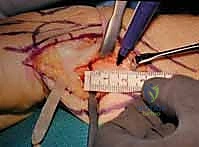

- The Distal Cut: We plan the first cut just proximal to the metaphyseal flare of the ulnar head. We must ensure we are entirely proximal to the articular surface of the DRUJ, yet distal enough to leave a robust block of bone that can accommodate two 3.5 mm or 4.0 mm screws. We verify this level with fluoroscopy. Using a small oscillating microsaw with a fresh blade, we make a clean, perpendicular cut across the ulnar shaft. Copious, continuous saline irrigation is applied directly to the blade to prevent thermal necrosis of the bone, which could compromise our arthrodesis.

- The Proximal Cut: Based on our preoperative measurements, we measure proximally from our first cut to mark the second osteotomy. If the patient has 3 mm of positive ulnar variance and we desire a final pseudoarthrosis gap of 12 mm, we must resect a total of 15 mm of bone. We mark the bone, verify with fluoroscopy, and make the second perpendicular cut. The cylindrical segment of the ulnar diaphysis is then removed and discarded (or saved as local autograft if needed for the arthrodesis site).

Joint Preparation and Arthrodesis

Clinical & Radiographic Imaging Archive